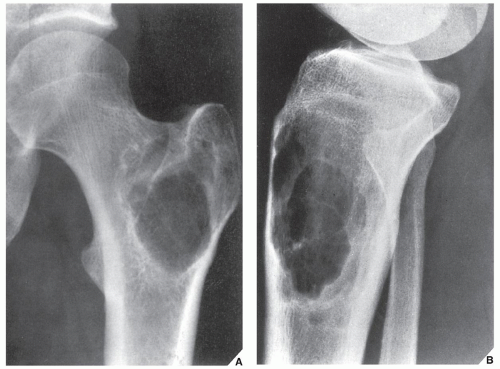

Рентгеновские снимки доброкачественных опухолей костей